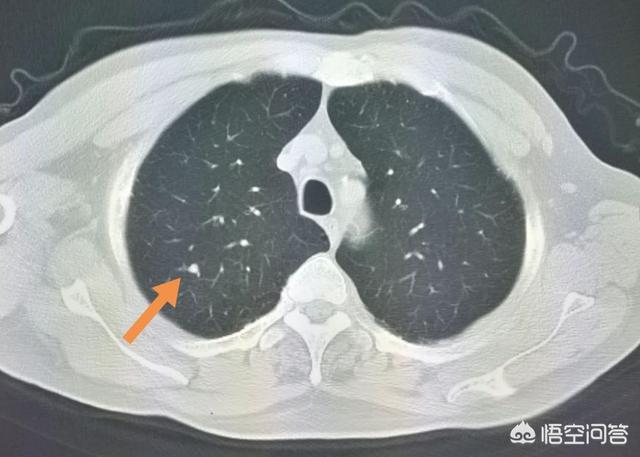

L'étape suivante consiste à déterminer la nature bénigne ou maligne des nodules pulmonaires. Les nodules bénins ne sont en aucun cas des ganglions lymphatiques dans les poumons, des tumeurs difformes, des pneumocytomes sclérosants, etc. Les nodules restants sont ceux qui peuvent être bénins ou malins, et le principe général du traitement de ces nodules est de recommander un suivi, avec un délai de révision allant de 3 mois à 1 an, en fonction des spécificités du nodule (morphologie, taille, densité, etc.). Certains nodules peuvent se résorber et disparaître au cours du suivi, comme les nodules inflammatoires, tandis que d'autres peuvent rester inchangés, comme les granulomes, ce qui est une bonne information. Si des signes de malignité apparaissent au cours du suivi, tels que l'élargissement du nodule, l'augmentation des composants réels ou solides dans le nodule de verre dépoli, un nodule plus dense, ou la présence de vaisseaux sanguins périphériques qui se développent, etc. En fait, c'est comme regarder les gens, un visage de droiture est généralement une bonne personne, une mauvaise personne féroce et vicieuse, et certains temporaires ne peuvent être vus que par l'observation du comportement de la personne, si les règles ne sont généralement pas effrayées, et si vous trouvez qu'il y a un mauvais comportement devrait être traité en temps opportun. Figure 1, nodule de verre dépoli dans la partie supérieure du poumon gauche (flèche orange), suivi pendant plus de deux ans sans changement. Figure 2, deux petits nodules de verre dépoli dans la partie supérieure du poumon droit (flèches orange), qui ont disparu après deux ans. Figure 3, nodule en verre dépoli dans la partie supérieure droite du poumon, qui a grossi au cours du troisième suivi, il est recommandé de le traiter positivement, et la pathologie chirurgicale du carcinome in situ, c'est-à-dire des lésions précancéreuses, peut réellement tuer le cancer du poumon dans l'œuf.